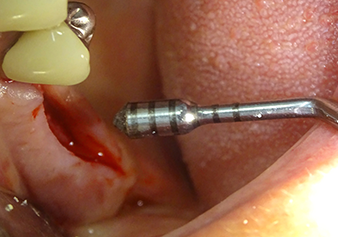

The I2A instrument (diameter 2.0 mm) was then used to perforate the sinus floor intermittently and on the smallest scale possible. This special piezosurgical method ensures that the Schneiderian membrane is not damaged. When the Z25P was used, the membrane was already lifted slightly by the coolant supplied via the instrument tip (Fig. 3). The coolant quantity was just 50% in order to avoid high pressure in the implant bed.

Implant bed preparation and augmentation

Following an intermediate check (Fig. 4) a further preparation step was performed (Fig. 5). Afterwards, the hydraulic Z35P instrument was used to lift the membrane to the desired position (Fig. 6 and 7). This was followed by further piezosurgical preparation of the implant bed, concluded with a rotary bur and shoulder milling cutter up to the implant diameter of 4.8 mm. Before the implant was inserted, the augmentation material (particle size approx. 0.8-1.6 mm) was introduced underneath the Schneiderian membrane (Fig. 8).